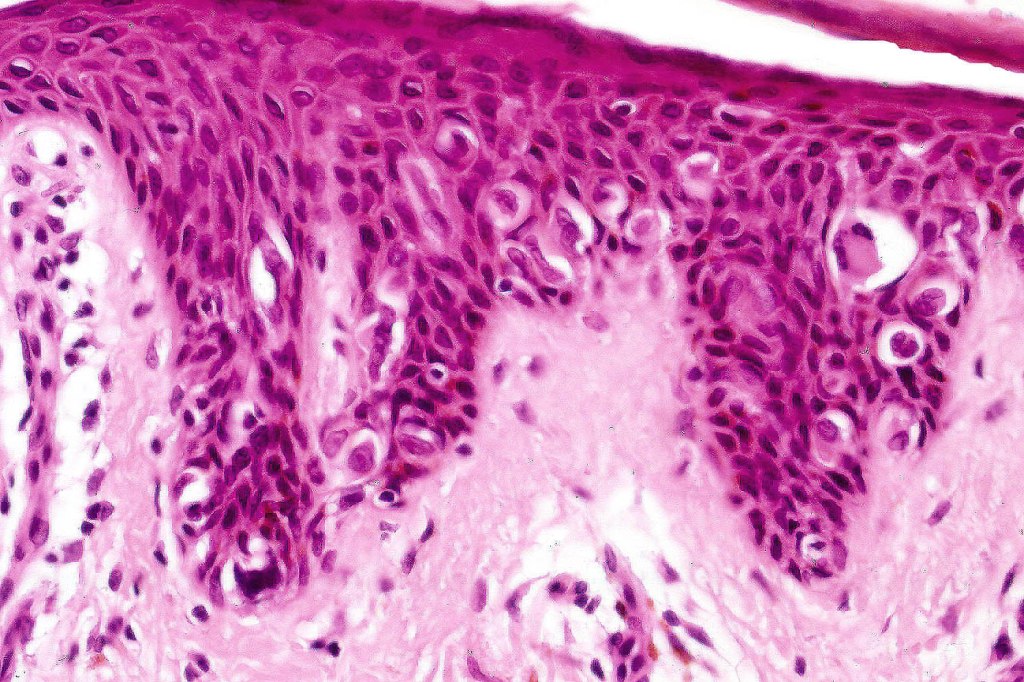

Histological features

•Variable acanthosis

•Intraepidermal proliferation of epithelioid Pagetoid cells with plentiful eosinophilic cytoplasm & vesicular nuclei with conspicuous eosinophilic cytoplasm

.Retraction artifact

•No mitoses